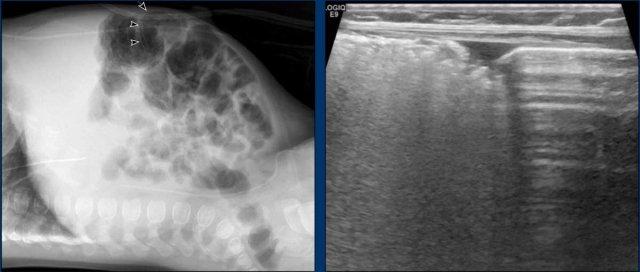

Hình ảnh

Hai phim X-quang chụp cách nhau vài giờ cho thấy ở vùng bụng trên chỉ có các quai ruột giãn nhẹ nhưng không có nếp niêm mạc, không thay đổi theo thời gian. Đây là dấu hiệu của vắng mặt nhu động ruột.

Lịch chụp lại được khuyến cáo là mỗi 6-8 giờ, nhưng tất nhiên phụ thuộc vào tình trạng lâm sàng.

Một ví dụ khác về quai ruột cố định.

Cuộn qua các hình ảnh.